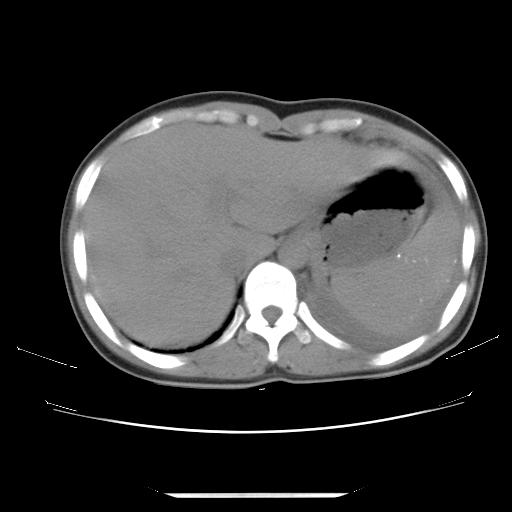

女,29岁,胸部不适,在外院胸片提示胸腔积液,到我院ct检查。

纵膈窗

左肺上叶不张,左侧胸水,叶间裂积液,纵隔淋巴结,脾脏钙化,考虑左肺上叶支气管内膜结核,结核性胸膜炎,脾结核

支持两肺继发性肺结核,左侧胸膜腔包裹性积液、胸膜肥厚,脾内多发钙化(结核钙化)。

右肺多发结节。左胸腔多发包裹性积液。